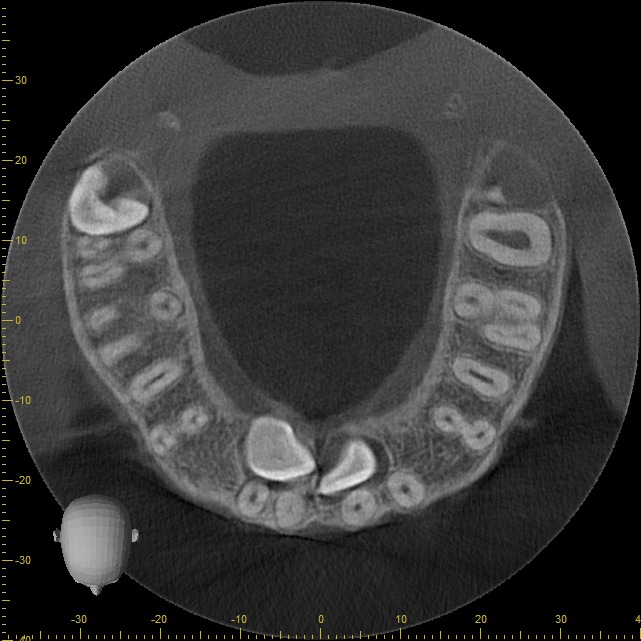

En nuestra clínica en Bogotá contamos con equipos de tomografía CBCT de última generación, que garantizan la más alta calidad en diagnóstico dental y permiten a tu odontólogo planificar cada detalle de tu tratamiento con máxima precisión.

• Rápido – Cómodo – Eficaz: Las imágenes obtenidas con nuestros equipos son altamente detalladas, mostrando los tejidos duros sin perder calidad.

• Baja radiación: Nuestros equipos toman imagenes en menos de un minuto, son completamente indoloros y la dosis de radiación es 100 veces menor que la de un escáner CT tradicional.

Podemos analizar la posición y orientación de estructuras críticas como los nervios, las raíces dentales, los senos paranasales y la nariz, lo que ayuda a lograr un diagnóstico lo más preciso posible. Con nuestra tecnología de imagen avanzada, tu odontólogo podrá monitorear la estabilidad a largo plazo de tus restauraciones dentales, de esta forma se podrá obtener el resultado estético que deseas con tu tratamiento.